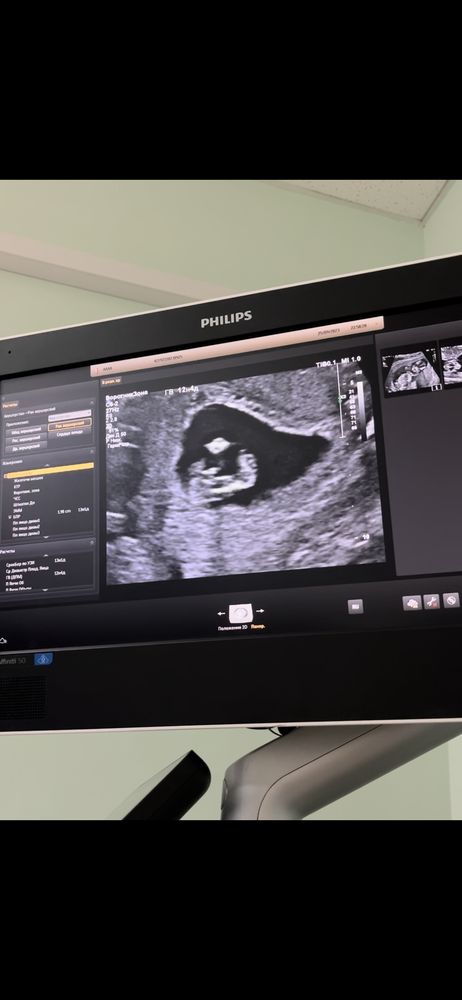

1 скрининг

Вчера был первый скрининг , я так поняла , что даже сомневаться не стоит кто там сидит 😄 узитска сказала « конфета приличная уже» 😂

Ну в 13 недель так не смотрят. Возможно, врач под другим углом увидела, а вам просто показала, чтоб не морочить голову углами). С парнями ошибка практически равна 0. Редко , когда конфета в пирожок превращается😁. Поздравляю с хорошим узи

какая там конфета,если половой бугорок что у мальчиков,что у девочек. Смотрят по его наклону. Да и не видно ничего) Но если врач сказал пол,то уже есть предположения